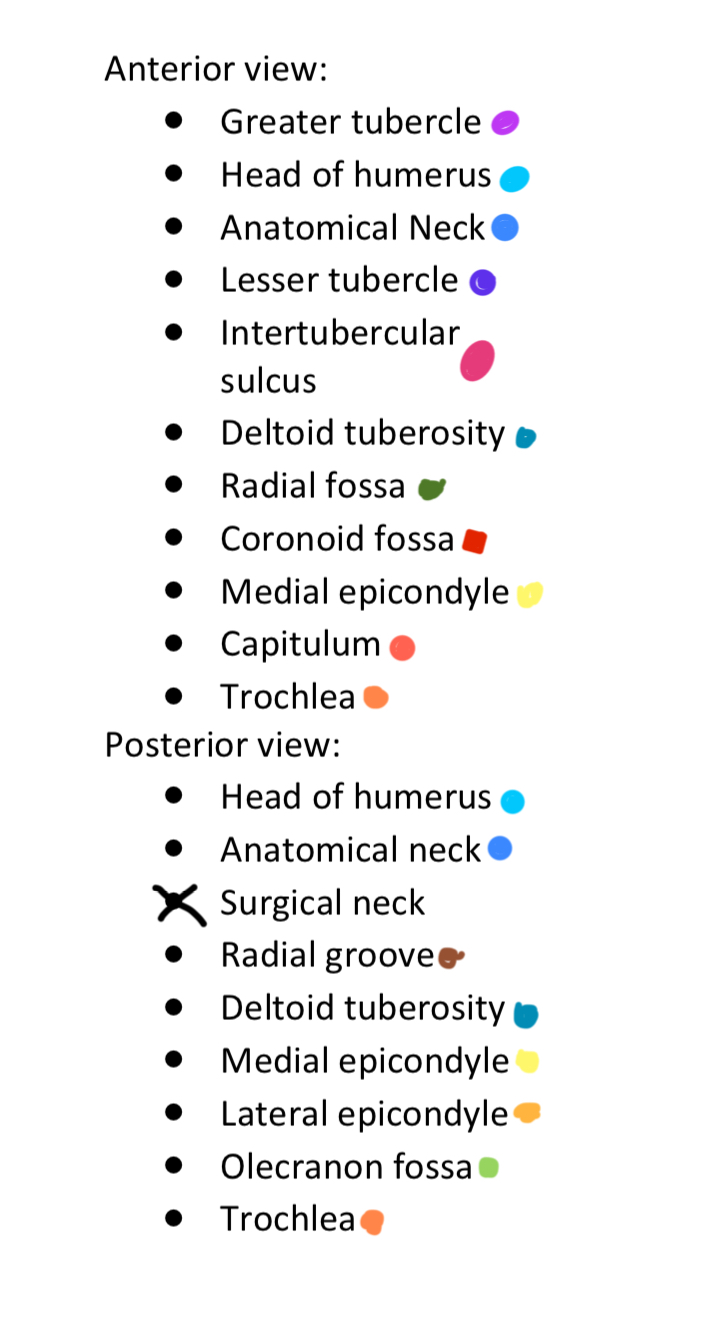

Anterior & Posterior Views of the Humerus

14 Terms

1

New cards

Light Purple

Greater Tubercle

2

New cards

Light Blue

Head of Humerus

3

New cards

Dark Blue

Anatomical Neck

4

New cards

Dark Purple

Lesser Tubercle

5

New cards

Pink

Intertubercular Sulcus

6

New cards

Cyan

Deltoid Tuberosity

7

New cards

Dark Green

Radial Fossa

8

New cards

Red

Coronoid Fossa

9

New cards

Yellow

Medial Epicondyle

10

New cards

Salmon

Capitulum

11

New cards

Dark Orange

Torchlea

12

New cards

Brown

Radial Groove

13

New cards

Light Orange

Lateral Epicondyle

14

New cards

Light Green

Olecranon Fossa